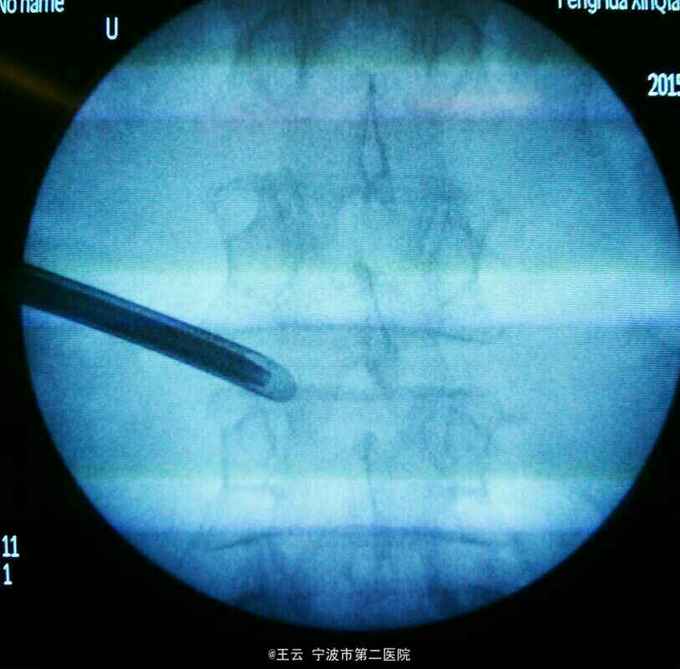

诊断:L3/4椎间盘脱出 治疗:经椎间孔入路椎间孔镜下髓核摘除,射频消融